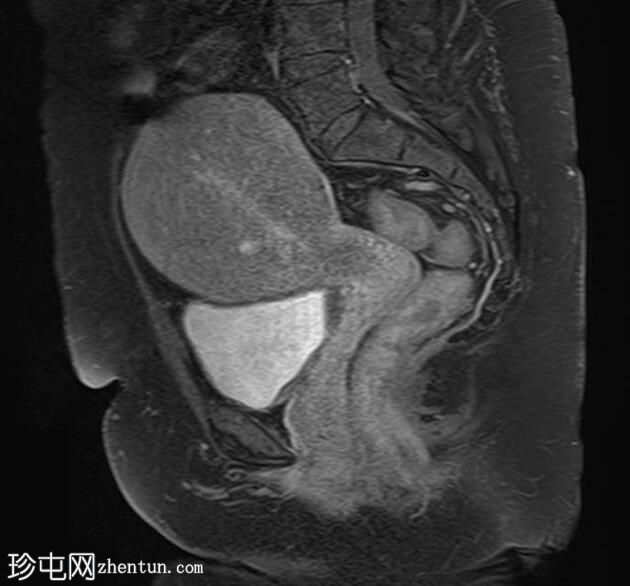

轴位T1加权像

增强脂肪抑制像

矢状位T1加权像

子宫增大,子宫内膜-肌层交界区弥漫性增厚,T1加权像呈中等信号,最高达45 mm;T2加权像呈低信号,内含多个小的高T2信号灶,提示月经出血渗入异位子宫内膜组织,符合弥漫性子宫腺肌症的

影像

学表现。

卵巢可见多个小的单房囊肿,无分隔或实性成分,最可能是浆液性包涵囊肿。

MRI表现最符合弥漫性子宫腺肌症。